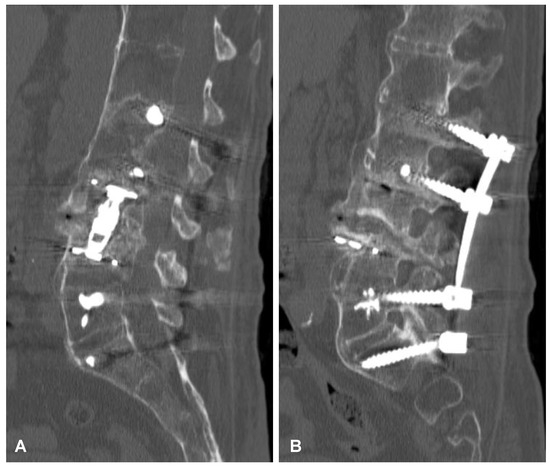

Figure 5. Postoperative sagittal CT scans (non-contrast enhanced) after the two-stage surgery of the lumbar spine demonstrating placement of the distractible vertebral body replacement implant between L3 and L4 (A) and posterior percutaneous transpedicular stabilization at the L2-L3-L5-S1 levels (B).

Figure 6. Postoperative CT-based reconstruction of the lumbar spine demonstrating correct positioning of the anterior and posterior spinal implants at the L2-L3-L5-S1 levels (A,B).

After initial diagnostics and preparations, the patient was transferred to the operating room. The posterior percutaneous transpedicular stabilization at the L2-L3-L5-S1 levels (Mantis; Stryker, Kalamazoo, MI, USA) with cement augmentation (VertaPlex HV; Stryker, Kalamazoo, MI, USA) for each inserted screw (4 mm × 6.5 mm/50 mm; 4 mm × 6.5 mm/45 mm) under intraoperative 2-dimensional (2-D) fluoroscopy control was performed in the first stage of surgery. In the second stage of surgery, from a lateral approach, the left side of the retroperitoneal cyst was emptied, and watery/light yellow fluid similar to urine was obtained. Therefore, a distractible vertebral body replacement implant (AsterX; Medtronic, Minneapolis, MN, USA) was placed between the L3 and L4 bodies with the placement of a retroperitoneal precutaneus Redon drainage system. A control CT scan performed one day after the operation revealed the correct placement of all the implants (Figure 5 and Figure 6). The second CE-CT scan performed two days after surgery consecutively showed evidence of post-traumatic right ureteral injury, urine leakage, and hydronephroureter (Figure 7). The general examination of intraoperatively obtained fluid revealed the following results: pH: 9.0; protein: 600 mg/dL; transparency and color before centrifugation: sanguine and cloudy; transparency and color before centrifugation: transparent and dark yellow; absolute leukocytes (LEU): 1197 cells/μL; and sediment: single round epithelium in the sample with erythrocytes loosely cover the field of vision (15–20 in the counterfield). The microbial culture of the intraoperative obtained fluid after 7 days was negative. After 4 days, the patient was transferred to another local hospital specializing in urological care. Due to the overall late presentation covering advanced hydronephrosis, ureteric stricture formation, and non-functional kidney, the nephrectomy and ureter ligation were performed. After urological treatment, the patient has been on follow-up for 2 years with no evidence of neurological or urological problems.